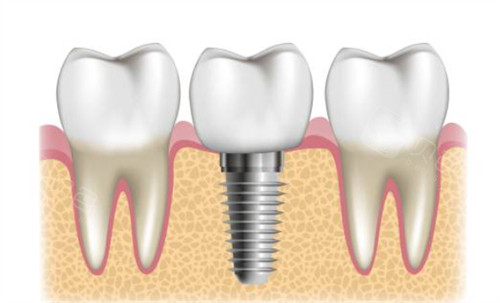

重度松动:若出现垂直向吸收或牙齿移位,可能需进入种植修复流程。